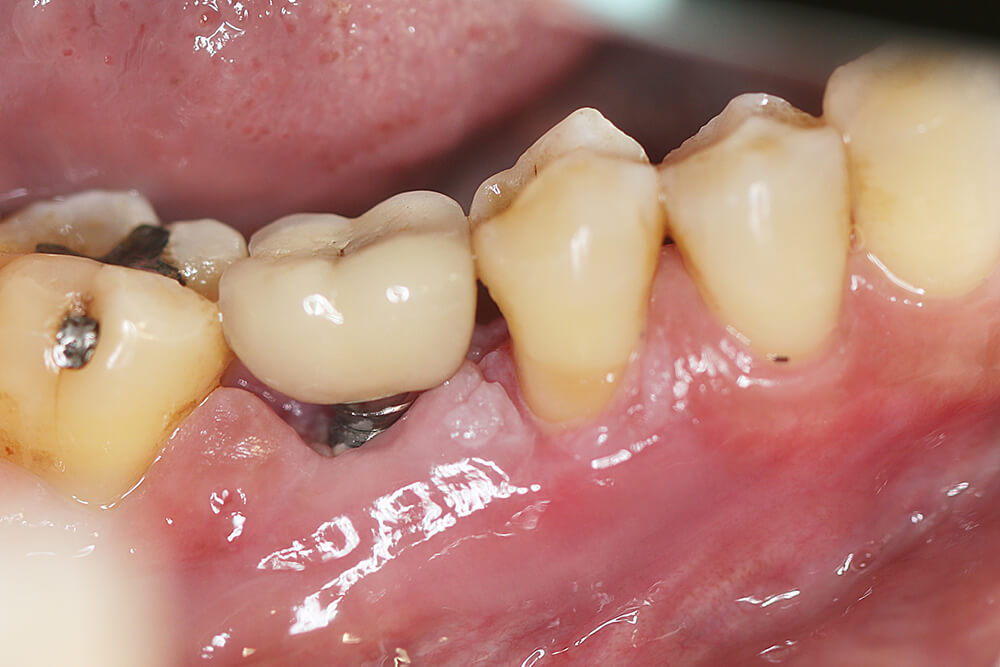

Q4. 植體周圍炎是什麼?

與植牙術後正常的牙齦發炎狀況不同,植體周圍炎可就不可輕忽了!簡單來說,您可以將植體周圍炎視為「植牙的牙周病」,主要原因是細菌感染讓植牙周遭組織被破壞,當齒槽骨被嚴重侵蝕無法支撐植體,就會面臨需移除植體、植牙失敗的地步。在此也提供植體周圍炎的原因,讓您深入了解並防範:

1. 細菌感染

如前面提到的,植體周遭細菌累積是造成植牙周圍炎主因。初期症狀是牙齦發炎,嚴重時齒槽骨開始流失,引發植體周圍炎。植體表面粗糙,很容易被細菌附著,同時,因其缺乏神經及牙周韌帶,很容易被忽視而延誤治療。